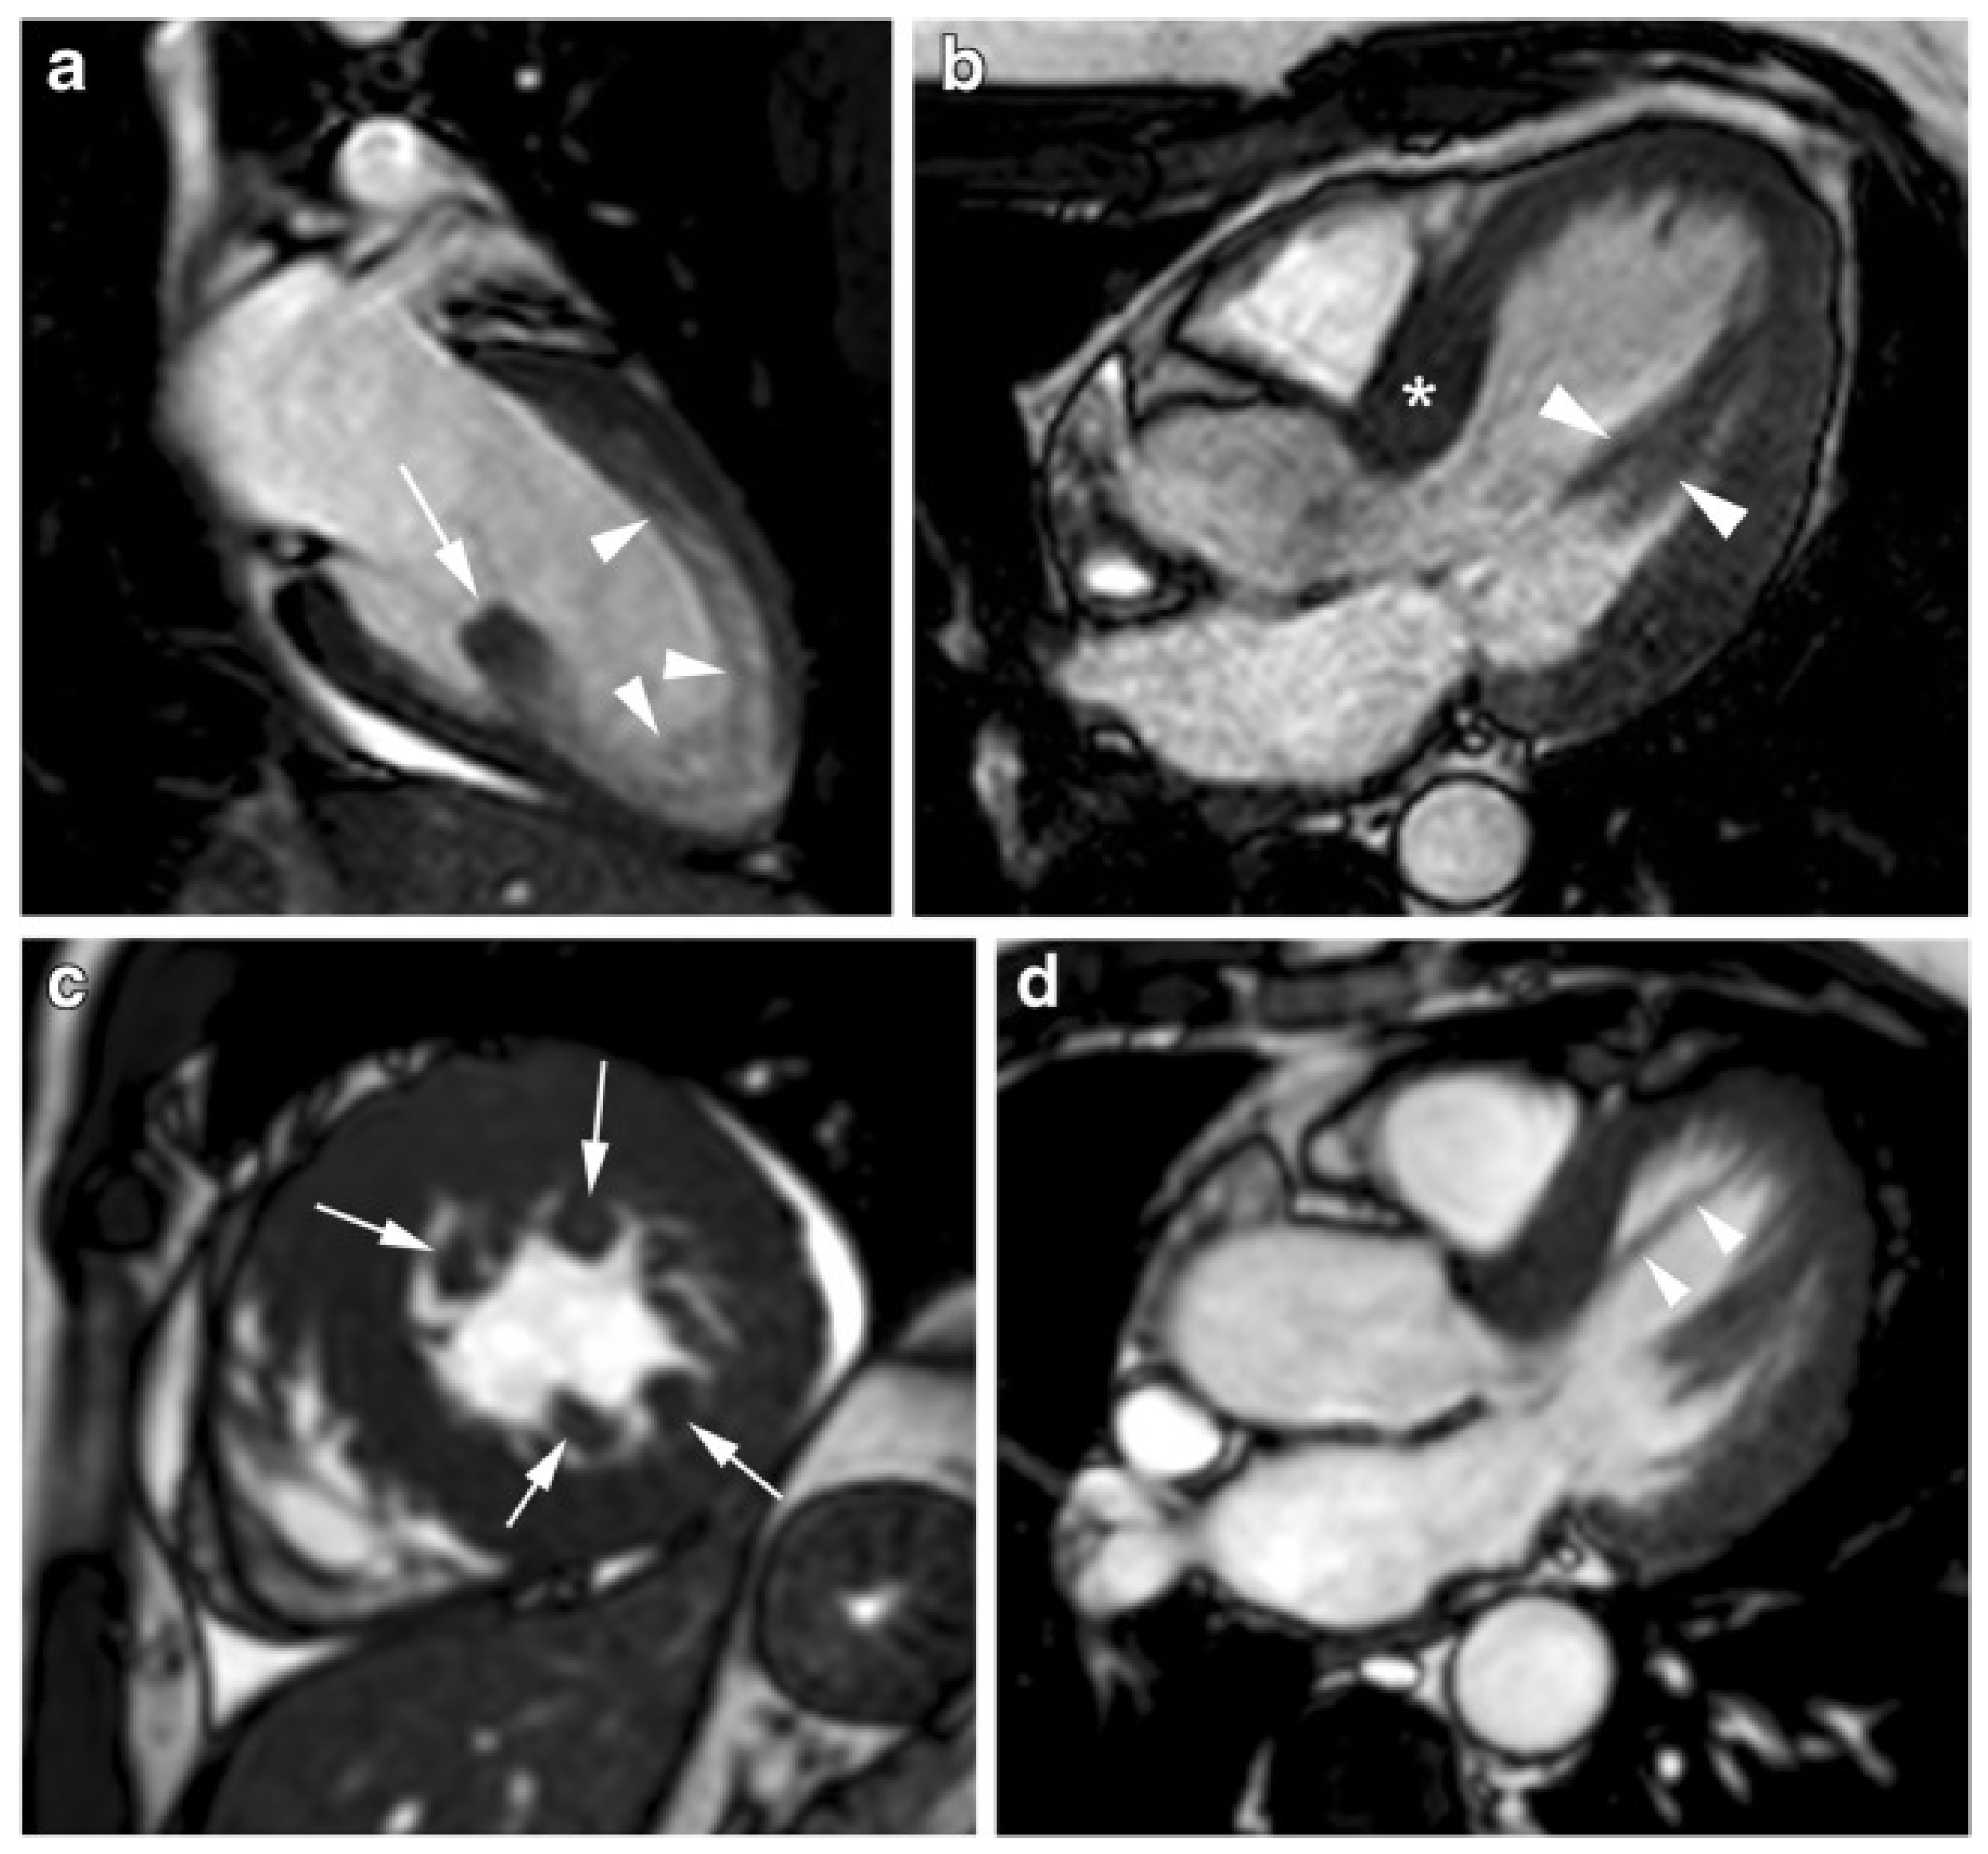

4. CMR Differential Diagnosis of Thickened Myocardium

4.1. Differential Diagnosis with Athlete’s Heart

4.2. Differential Diagnosis with Hypertensive Heart Disease

4.3. Differential Diagnosis with Infiltrative Cardiomyopathies